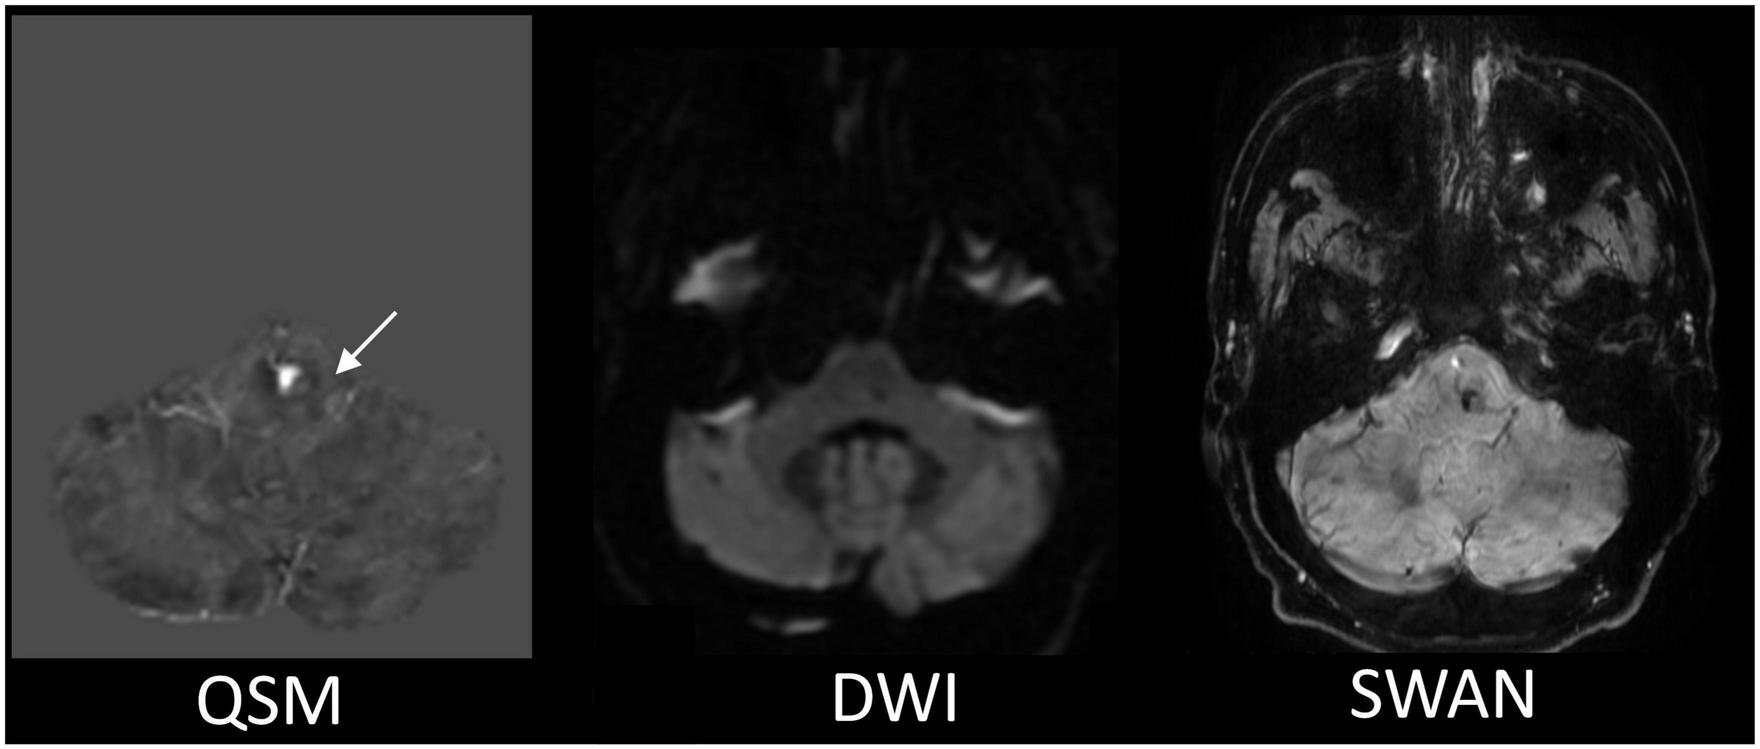

Among the multiple acquired MR sequences, QSM demonstrated the highest level of sensitivity for CCM (Figure 2). Average CCM lesion sizes measured on QSM ranged from 68.0 mm3 to 2.3 cm3. CCM lesion location and each patient’s average within-lesion flutriciclamide SUVs are presented in Table 3. The average flutriciclamide SUV and QSM values were 0.58 ± 0.23 g/ml and 0.30 ± 0.10 ppm, respectively, among 17 CCM lesions. The average image contrast ratio of the flutriciclamide uptake in the CCM lesion over the remainder of the non-CCM brain tissue region in the vicinity was 6-7-fold high, as observed in the cross-section profile in Figure 3. Figure 4A shows the increased flutriciclamide uptake within two CCM lesions. Qualitatively, flutriciclamide uptake in CCM lesions was heterogeneous while CCM lesions were overall larger and could appear either heterogenous or uniformly hyperintense on QSM (Figures 4A, 5). SUV of flutriciclamide was positively correlated with QSM values within CCM lesions (r = 0.53, p = 0.03) as indicated in Figure 4B.

FIGURE 2

The representative MR images comparison for the CCM detection. The QSM displays the most apparent boundary of the CCM from among all the MR images we acquired. The white arrow is pointing to the location of the CCM.

Among the multiple MR images we obtained, QSM was the superior imaging technique for delineating CCM lesions (Figure 2). Our results aligned with those of previous studies (3, 21, 61), further substantiating QSM as an important surrogate marker for evaluating lesions in patients with CCM. Both neuroinflammation and iron deposition were observed simultaneously within CCM lesions, resulting in a moderate but significant correlation between these parameters. This suggests that ruptured CCM vasculature results in inflammation. As seen in Figures 4A, 5, the fact that respective distributions of neuroinflammation and iron deposition are spatially distinct, suggests that they provide separate but complementary information for future studies in CCM.